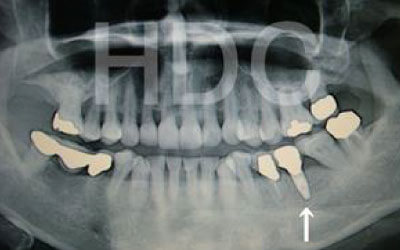

最も大きな違いは、前後の歯の寿命に影響が出ることです。

ブリッジの場合、抜けた歯の前後にある歯を、重度の虫歯と同じくらいまで削る必要があります。

また、抜けた歯の代わりに前後の歯が力を支えるため、その歯に常に1.5倍の負荷がかかります。

1)ブリッジ

2)歯を大きく削る+支えの歯に1.5倍の力がかかる

3)前後の歯の寿命が著しく減る

ブリッジの支えの歯は、データでは10年以内に68%が抜歯になります。